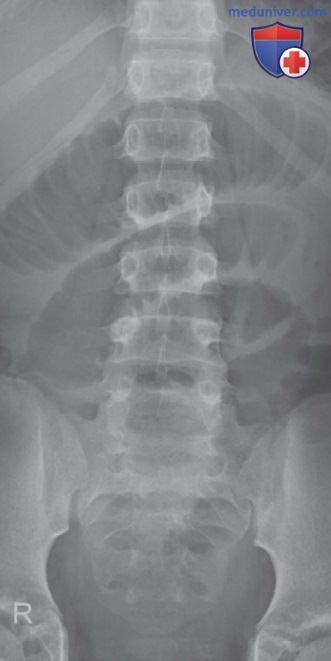

Рисунок 2. Рентгенограмма поясничного отдела позвоночника в ПЗ проекции, полученная с использованием периферических камер АКЭ.

- Недостаточная экспозиция возникнет при выборе камеры под структурой, характеризующейся меньшим количеством атомов, меньшей толщиной или плотностью, чем область ЗИ (рис. 2)